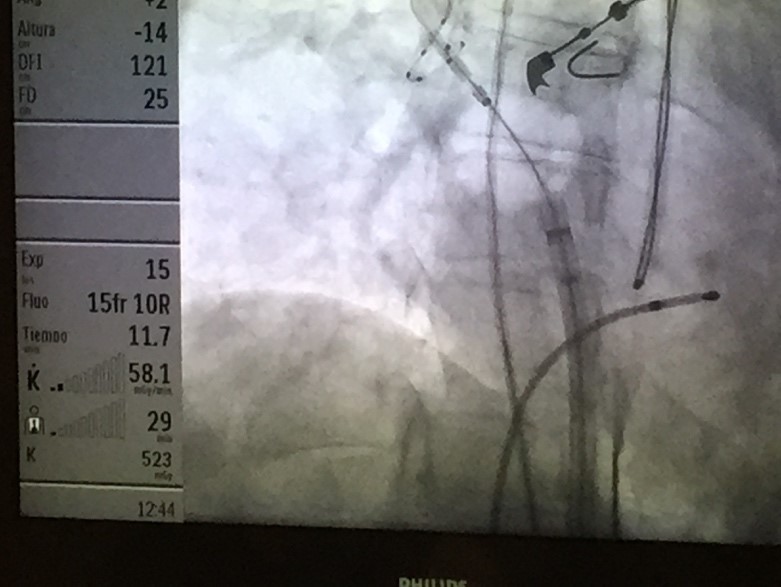

Figura 5: Imagen radiocópica de un caso en donde se observa el balón inflado en la Vena Pulmonar Superior Derecha inciando la aplicación luego de la eyección de contraste sin signos de fuga. Notese además el termometro midiendo la temperatura intraesofágica.